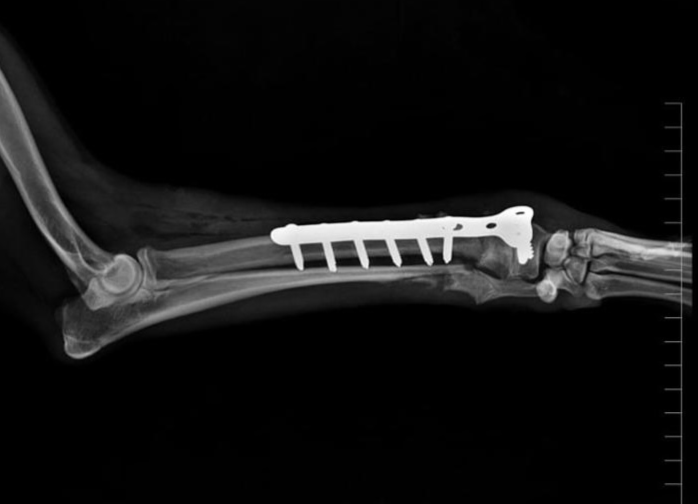

Distal Radial Fracture

A distal radial fracture is a break involving the lower third of the radius, often near or extending into the radiocarpal joint.

Fixation : distal radial fixation using T Plate